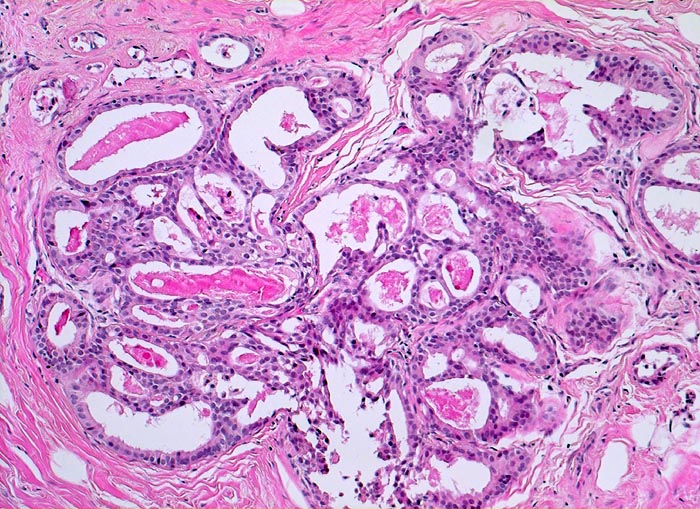

intraduktale Epithelproliferation ohne Atypie und Mikrokalk

Zellproliferation und Ausbildung unregelmässig geformter Hohlräume. Die Hohlräume sind mit eingedicktem Sekret gefüllt.

Probeexzision wegen umschriebenen Mikroverkalkungen in der Screeningmammographie. Bei der Palpation lassen sich mehrere unscharf begrenzte derbe Knoten tasten.

Histologie

100